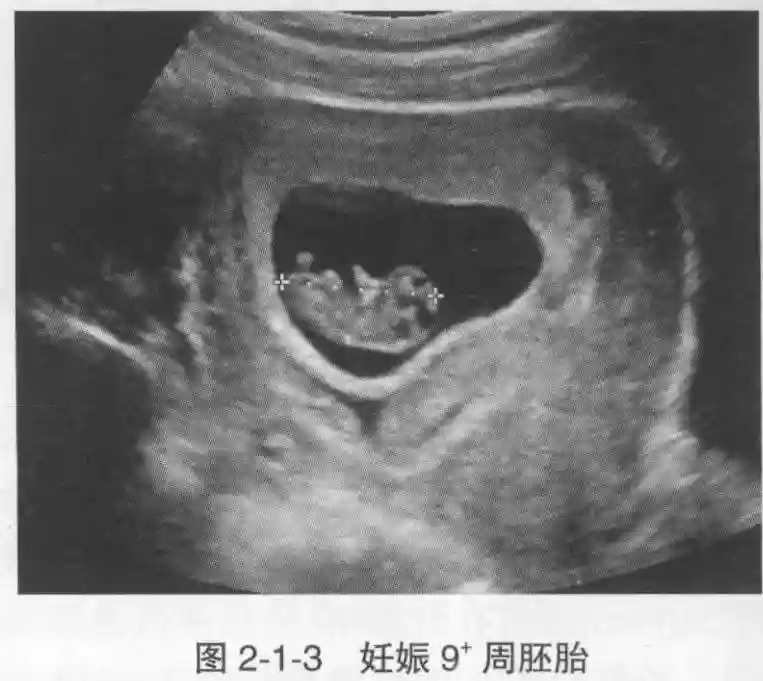

3??胚胎:胚胎通常在6-7周時(shí)可以為超聲顯示,起初為胎芽,表現(xiàn)為卵黃囊一側(cè)局部組織增厚,達(dá)到1 -2 mm 時(shí)才有可能為超聲測(cè)量出來(lái)。達(dá)4-5mm時(shí)可見(jiàn)胎心搏動(dòng),相應(yīng)孕周為6-6.5周,妊娠囊大小為13-18mm。胚芽長(zhǎng)度≥7㎜時(shí)仍未見(jiàn)心管搏動(dòng),提示胚胎停止發(fā)育。胚胎的出現(xiàn)和妊娠囊直徑的關(guān)系:妊娠囊直徑> 16 mm 時(shí),經(jīng)陰道超聲應(yīng)顯示胚胎。妊娠囊直徑> 25 mm 時(shí),經(jīng)腹超聲均應(yīng)顯示胚胎。

4??胎心搏動(dòng):胎心搏動(dòng)通常出現(xiàn)于6-6.5周,胚胎在4- 5mm就應(yīng)該顯示胎心搏動(dòng)。